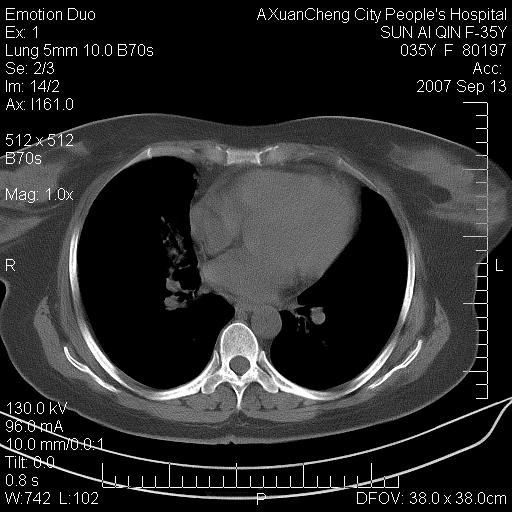

以下是引用天南地北在2007-9-13 13:43:00的发言:[br]考虑双肺、肺门侵润

以下是引用ydx_74在2007-9-13 15:42:00的发言:[br]仅看片,考虑右上肺癌并双肺转移,结合病史,考虑肺门、肺内淋巴侵润

以下是引用同在2007-9-13 15:08:00的发言:[br]支持肺门及双肺侵润.